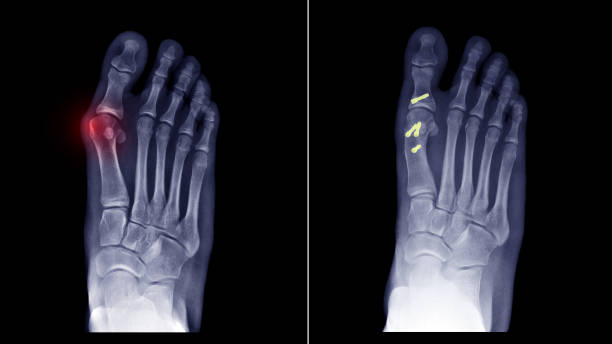

✅무지외반증 통증 아무도 모르는 관리법 8가지

✅무지외반증 통증 관리하는 법

무지 외반증은 초기에 적절한 관리와 운동을 통해 개선할 수 있는 상태입니다.